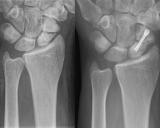

Новое исследование, представленное в журнале The Lancet, показало, что использование гипса так же эффективно при лечении переломов ладьевидной кости запястья, как и хирургическое вмешательство...